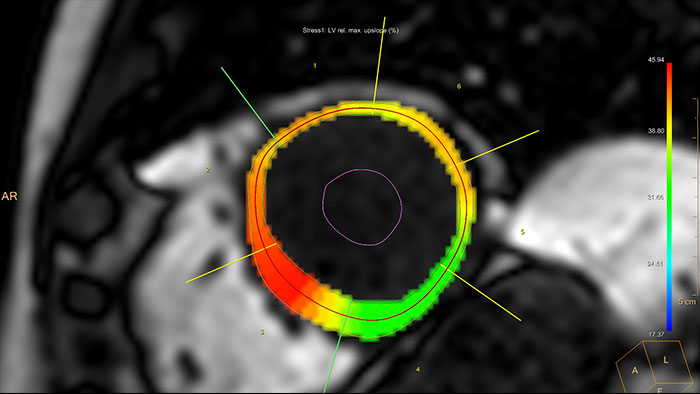

- Cardiac Temporal Enhancement

MR Cardiac Temporal Enhancement

Support assessing temporal enhancements of the myocardium

Facilitates myocardial analysis of dynamically resolved cardiac data (multi-slice, dynamics) and enables comparison of rest and stress studies.

Benefits

- Results are presented using either the AHA standardized or adapted bull’s eye views.

- The package includes a correction algorithm and manual tools to correct frame-to-frame heart displacements caused by breathing.